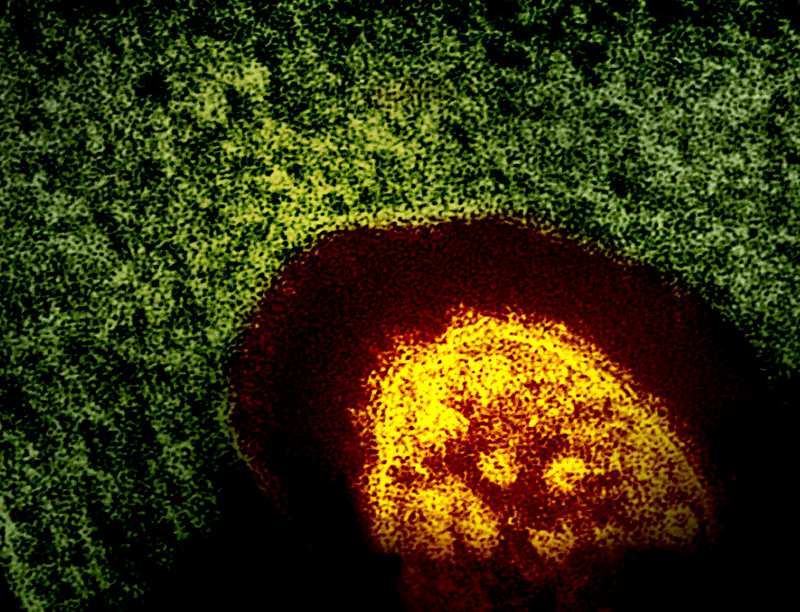

Measles is a highly contagious disease caused by a virus. It spreads through the air when an infected person coughs or sneezes. It can be very serious and cause hospitalizations, serious health complications and even death.

Before the measles vaccination program started in the U.S. in 1963, an estimated 3 million to 4 million people in the country got measles each year. Prior to the introduction of the vaccine, 48,000 people were hospitalized due to measles and nearly 500 died each year. Since then, widespread use of the measles vaccine has resulted in a greater than 99% reduction in measles cases and deaths compared to the pre-vaccine era. But outbreaks related to vaccine hesitancy have been occurring worldwide in recent years. In the U.S., more than 2,000 cases of measles were reported in 2025, the most number of cases since measles was declared eliminated in the U.S. in 2000.